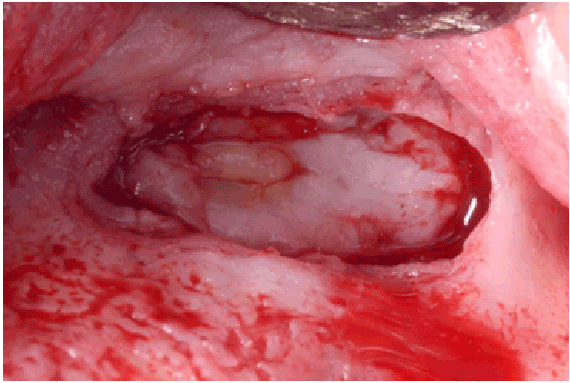

所有穿孔(>10 mm)在手术期间使用位于骨窗延伸后窦侧壁和穿孔的Scheiderian膜之间的可吸收胶原膜(collapape®,Integra LifeSciences Corp., Plainsboro, NJ)修复(图1f)。采用可吸收缝线(4-0 Chromic Gut, Johnson & Johnson, New Brunswick, NJ)完成皮瓣一期缝合(图1g和1h)。然后在3到6周的愈合时间后进行鼻窦再入路手术,以实现鼻窦增强手术。抬高全层皮瓣,暴露初始骨窗,需要剥离软组织(图2a),以便能够抬高愈合的施耐德膜(图2b)。由于在之前的手术中没有使用移植物材料来填充鼻窦,因此鼻窦被移植了无机牛骨基质(ABBM) (Bio-Oss®(图2c和2d)和可吸收膜(Bio-Guide)®,Geistlichpharma,Princeton,NJ)被放在窗户上方。

图1D:抬高皮瓣以暴露鼻窦手术部位

图1E:Schneiderian膜穿孔>10 mm

图1 f:位于窦壁和穿孔窦膜之间的可吸收胶原膜(CollaTape®)